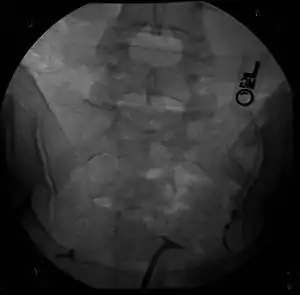

| Hysterosalpingography of a T-shaped uterus. | |

Women are often diagnosed with this condition after several failed pregnancies, proceeded by exploratory diagnostic procedures, such as magnetic resonance, sonography, and particularly hysterosalpingography.[6][7][8] In such studies, a widening of the interstitial and isthmus of uterine tube is observed, as well as constrictions or narrowing of the uterus as a whole, especially the lower and lateral portions, hence the "t" denomination. The uterus might be simultaneously reduced in volume, and other abnormalities might be concomitantly present.[9]